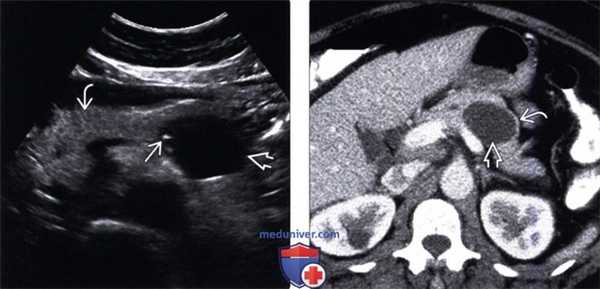

(Левый) На поперечном УЗ срезе брюшной полости в теле поджелудочной железы определяется четко отграниченное анэхогенное кистозное новообразование с единичными периферическими гиперэхогенными очагами. Обратите внимание на неизмененную поджелудочную железу.

(Правый) При КТ с контрастным усилением на аналогичной аксиальной томограмме в теле поджелудочной железы визуализируется кистозное образование овальной формы с контрастной капсулой. Внутри образования имеются перегородки, невидимые на КТ.